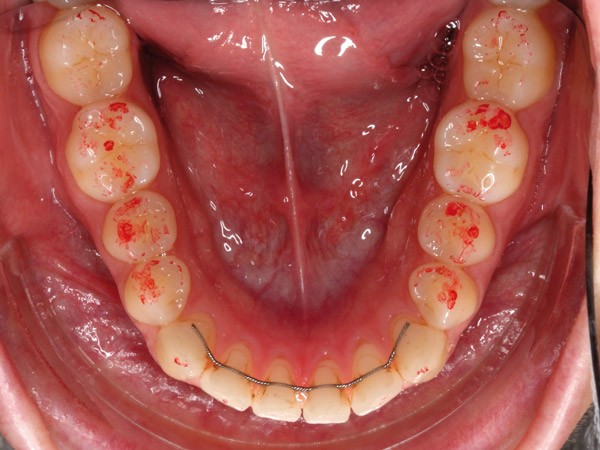

Ces différents aspects dépendent non seulement de la qualité et de l’épaisseur du papier, de son support, de la composition de l’encre, de l’imprégnation salivaire, mais aussi de la force de morsure [3-8]. En fonction du nombre de morsures et de la manière dont le patient serre sur le papier à articuler, la couleur, la taille et la forme des marques varient (fig. 1).

De plus, son utilisation répétée réduit significativement la précision et la sensibilité [4]. Même lorsque ces papiers sont employés dans des conditions idéales, les marques ne sont pas reproductibles [2-5, 9, 10] et le papier à articuler est souvent sujet à des perforations ou des déchirures lors des mouvements de fermeture en intercuspidie [9]. D’autre part, sur un champ humide, l’encre peut diffuser, ou le papier peut se plier, par exemple par retour du papier occlusal…